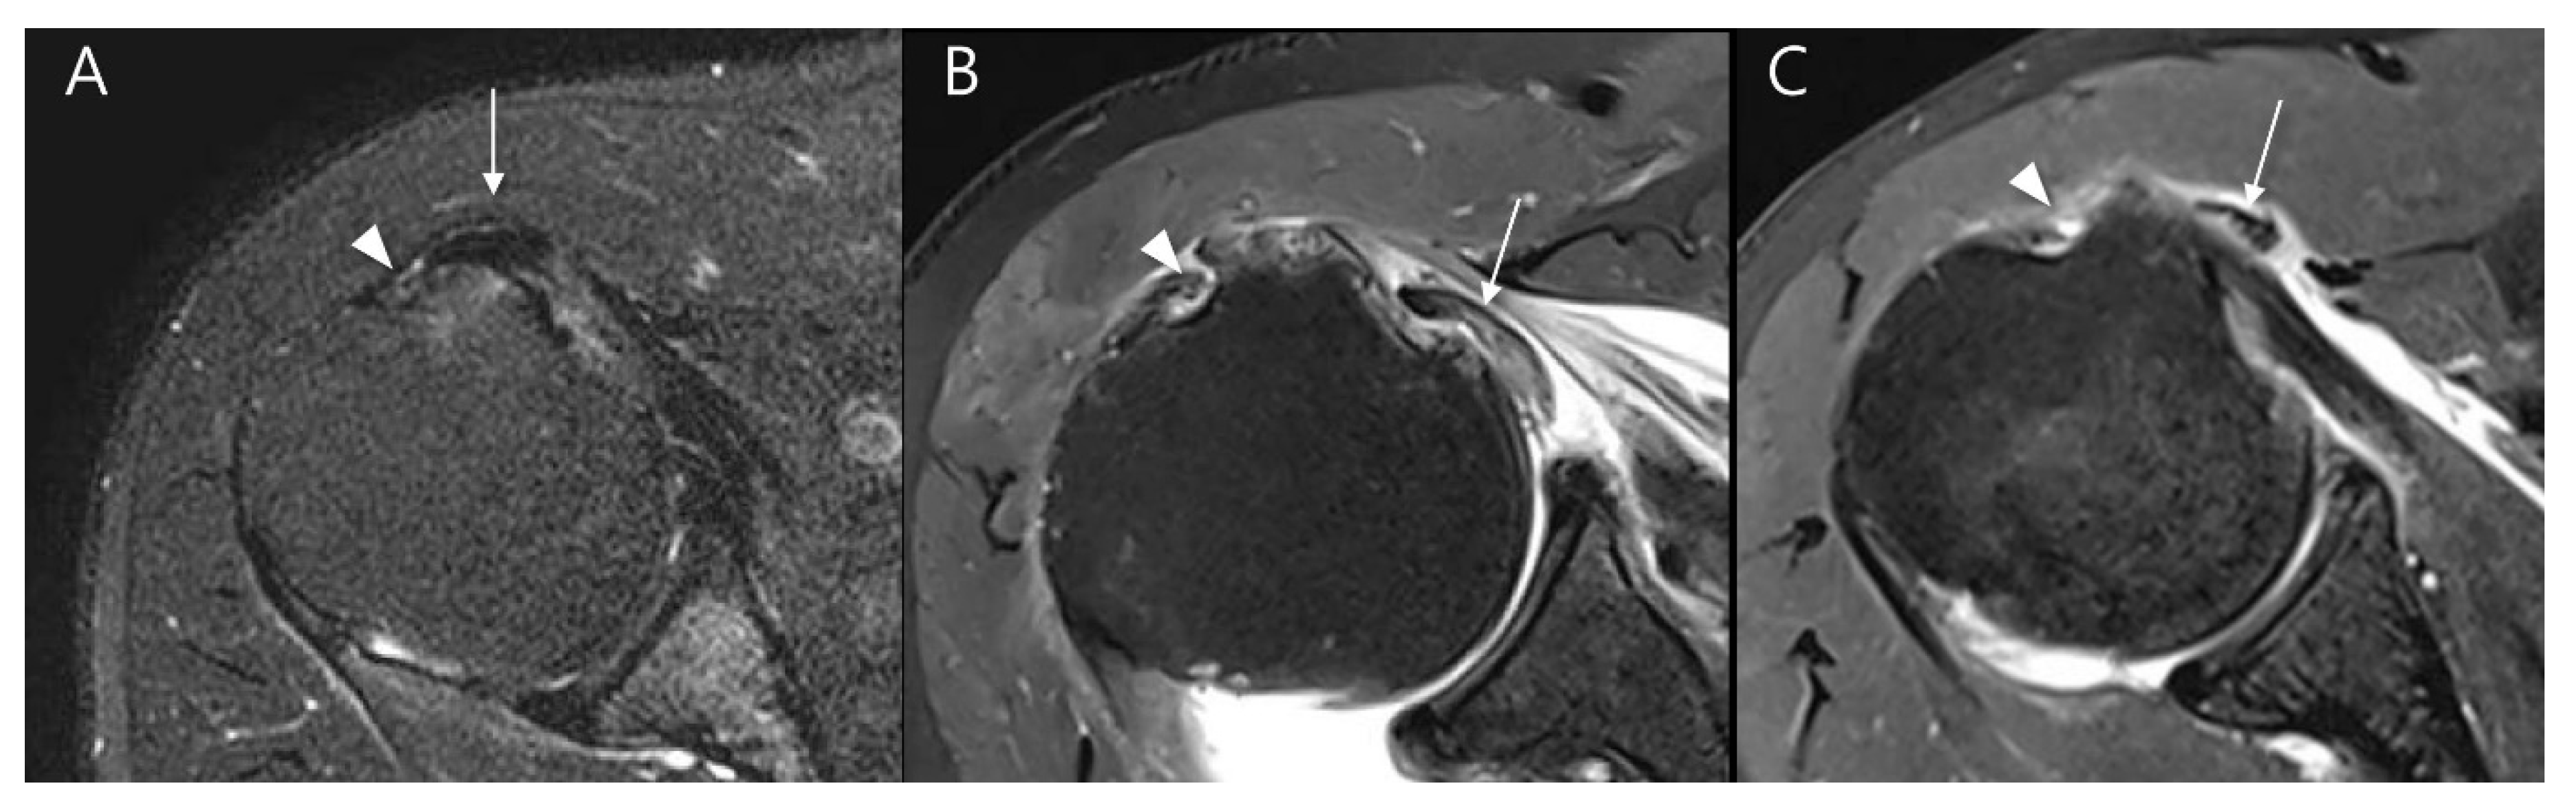

| Lesser tuberosity cyst (%) | 28 (25.2) | 15 (46.9) | 0.033 | κ = 1.000 (p < 0.001) |

| Full thickness tear (%) | 4 (3.6) | 5 (15.6) | 0.040 | κ = 1.000 (p < 0.001) |

| Partial thickness tear (%) | 47 (43.9) | 25 (92.6) | <0.001 | κ = 0.981 (p < 0.001) |

| Subluxation or dislocation (%) | 13 (12.1%) | 22 (81.5%) | <0.001 | κ = 0.853 (p < 0.001) |